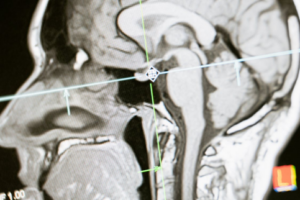

Trucking accidents are among the most serious and complex incidents on our highways, often causing severe injuries, fatalities, and significant financial burdens. Learn how an experienced California truck accident lawyer – like those at RMD Law – can fight to get victims the compensation they deserve.